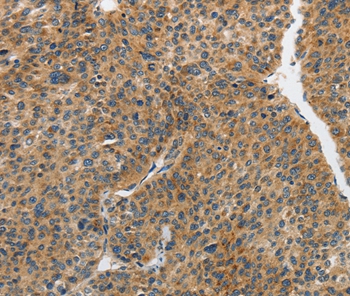

Immunohistochemical analysis of paraffin-embedded Human liver cancer tissue using #37375 at dilution 1/25.